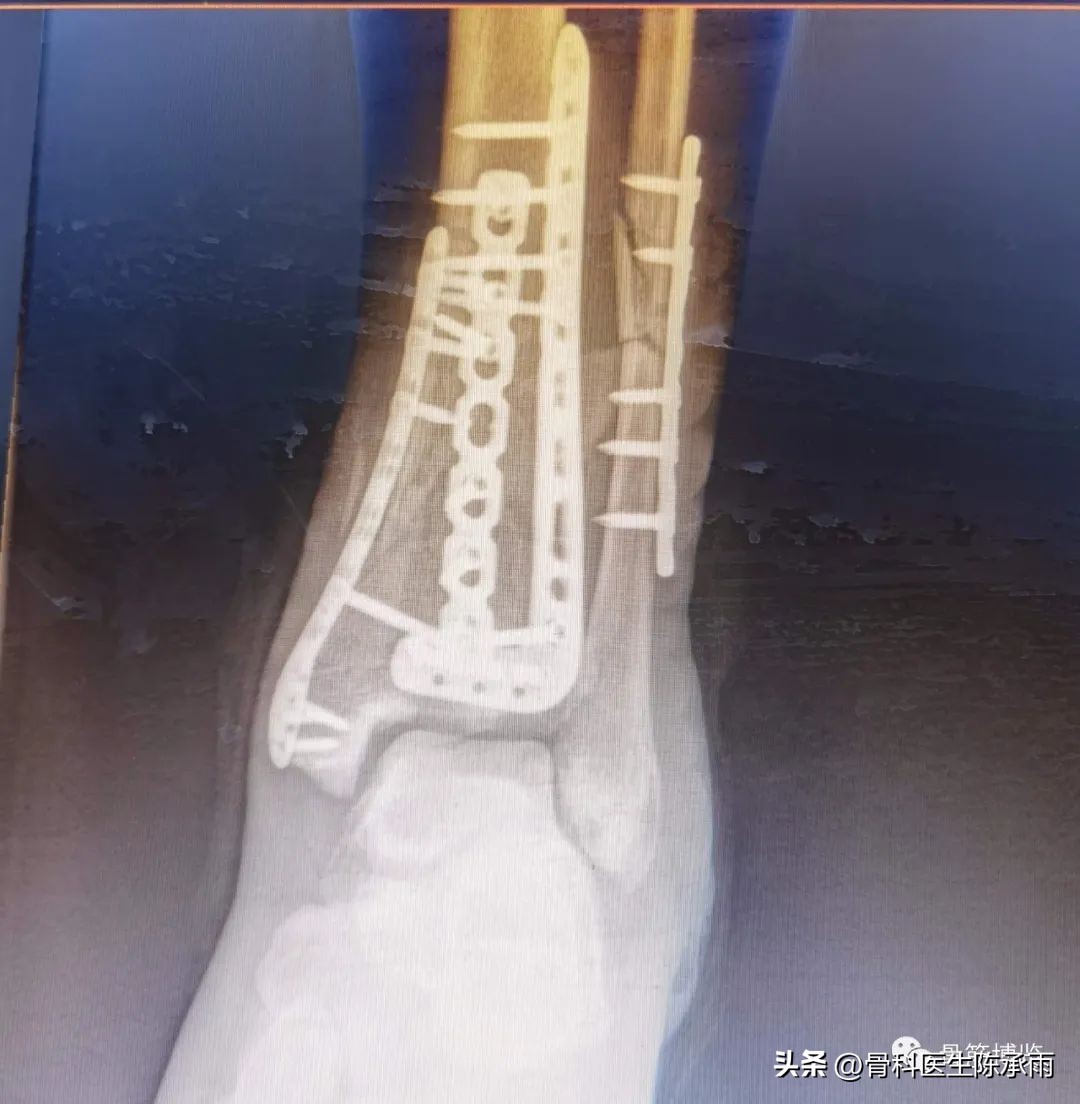

近日的1例股前外侧皮瓣修复查踝前皮肤缺损。